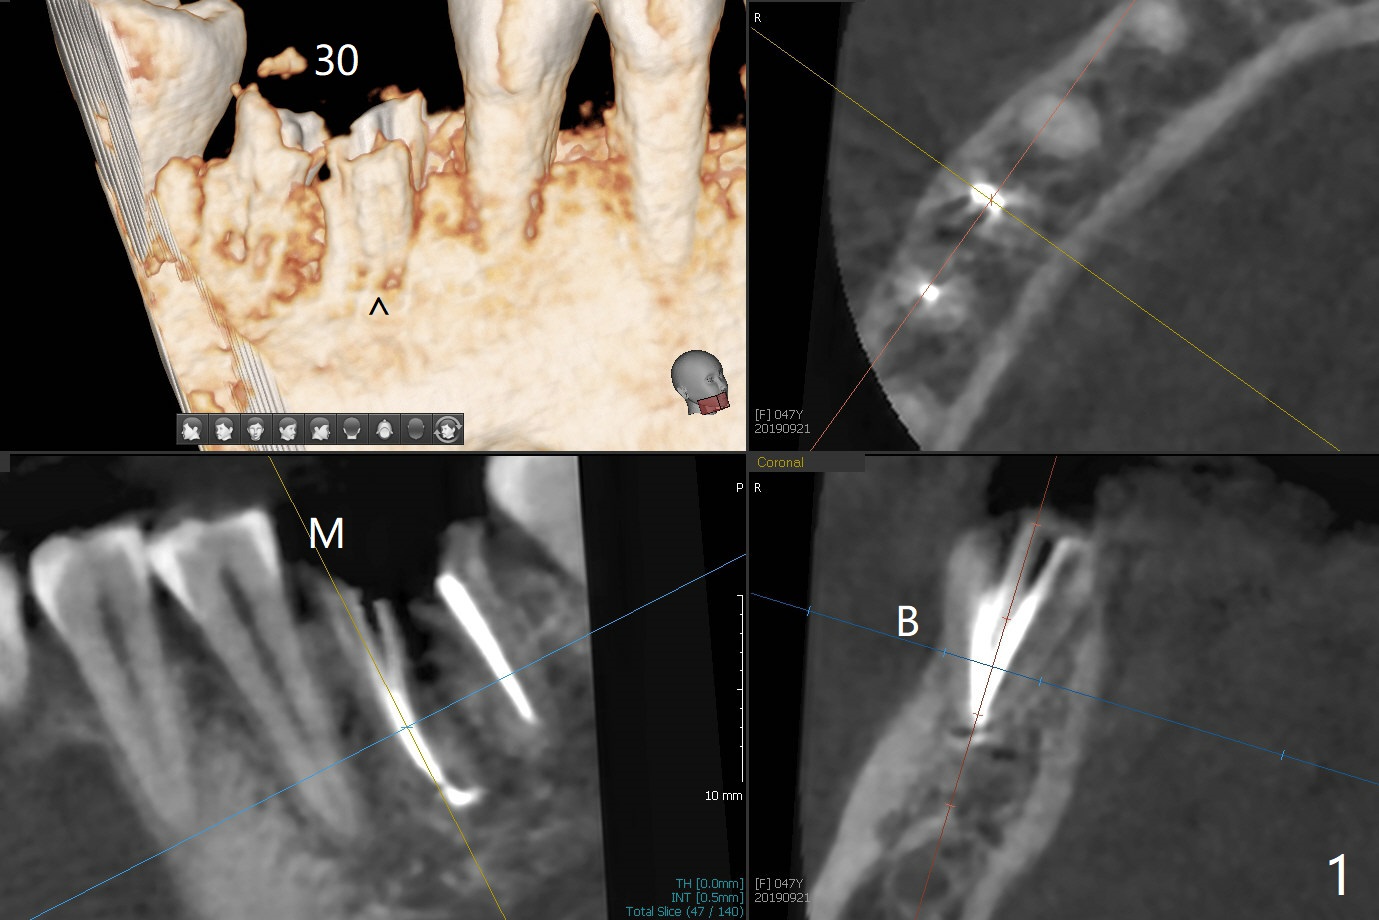

The tooth #30 of a 47-year-old woman has lower buccal crest (Fig.1-3 ^). To prevent post-extraction buccal plate collapse, closed socket shield (Fig.6,8-10 *) will be conducted in the mesial (Fig.1,4-6) and distal (Fig.2,7-10) roots. To decrease vibration, the buccal edge of the roots will be trimmed first (Fig.5,6 a) before root section (Fig.6 b).